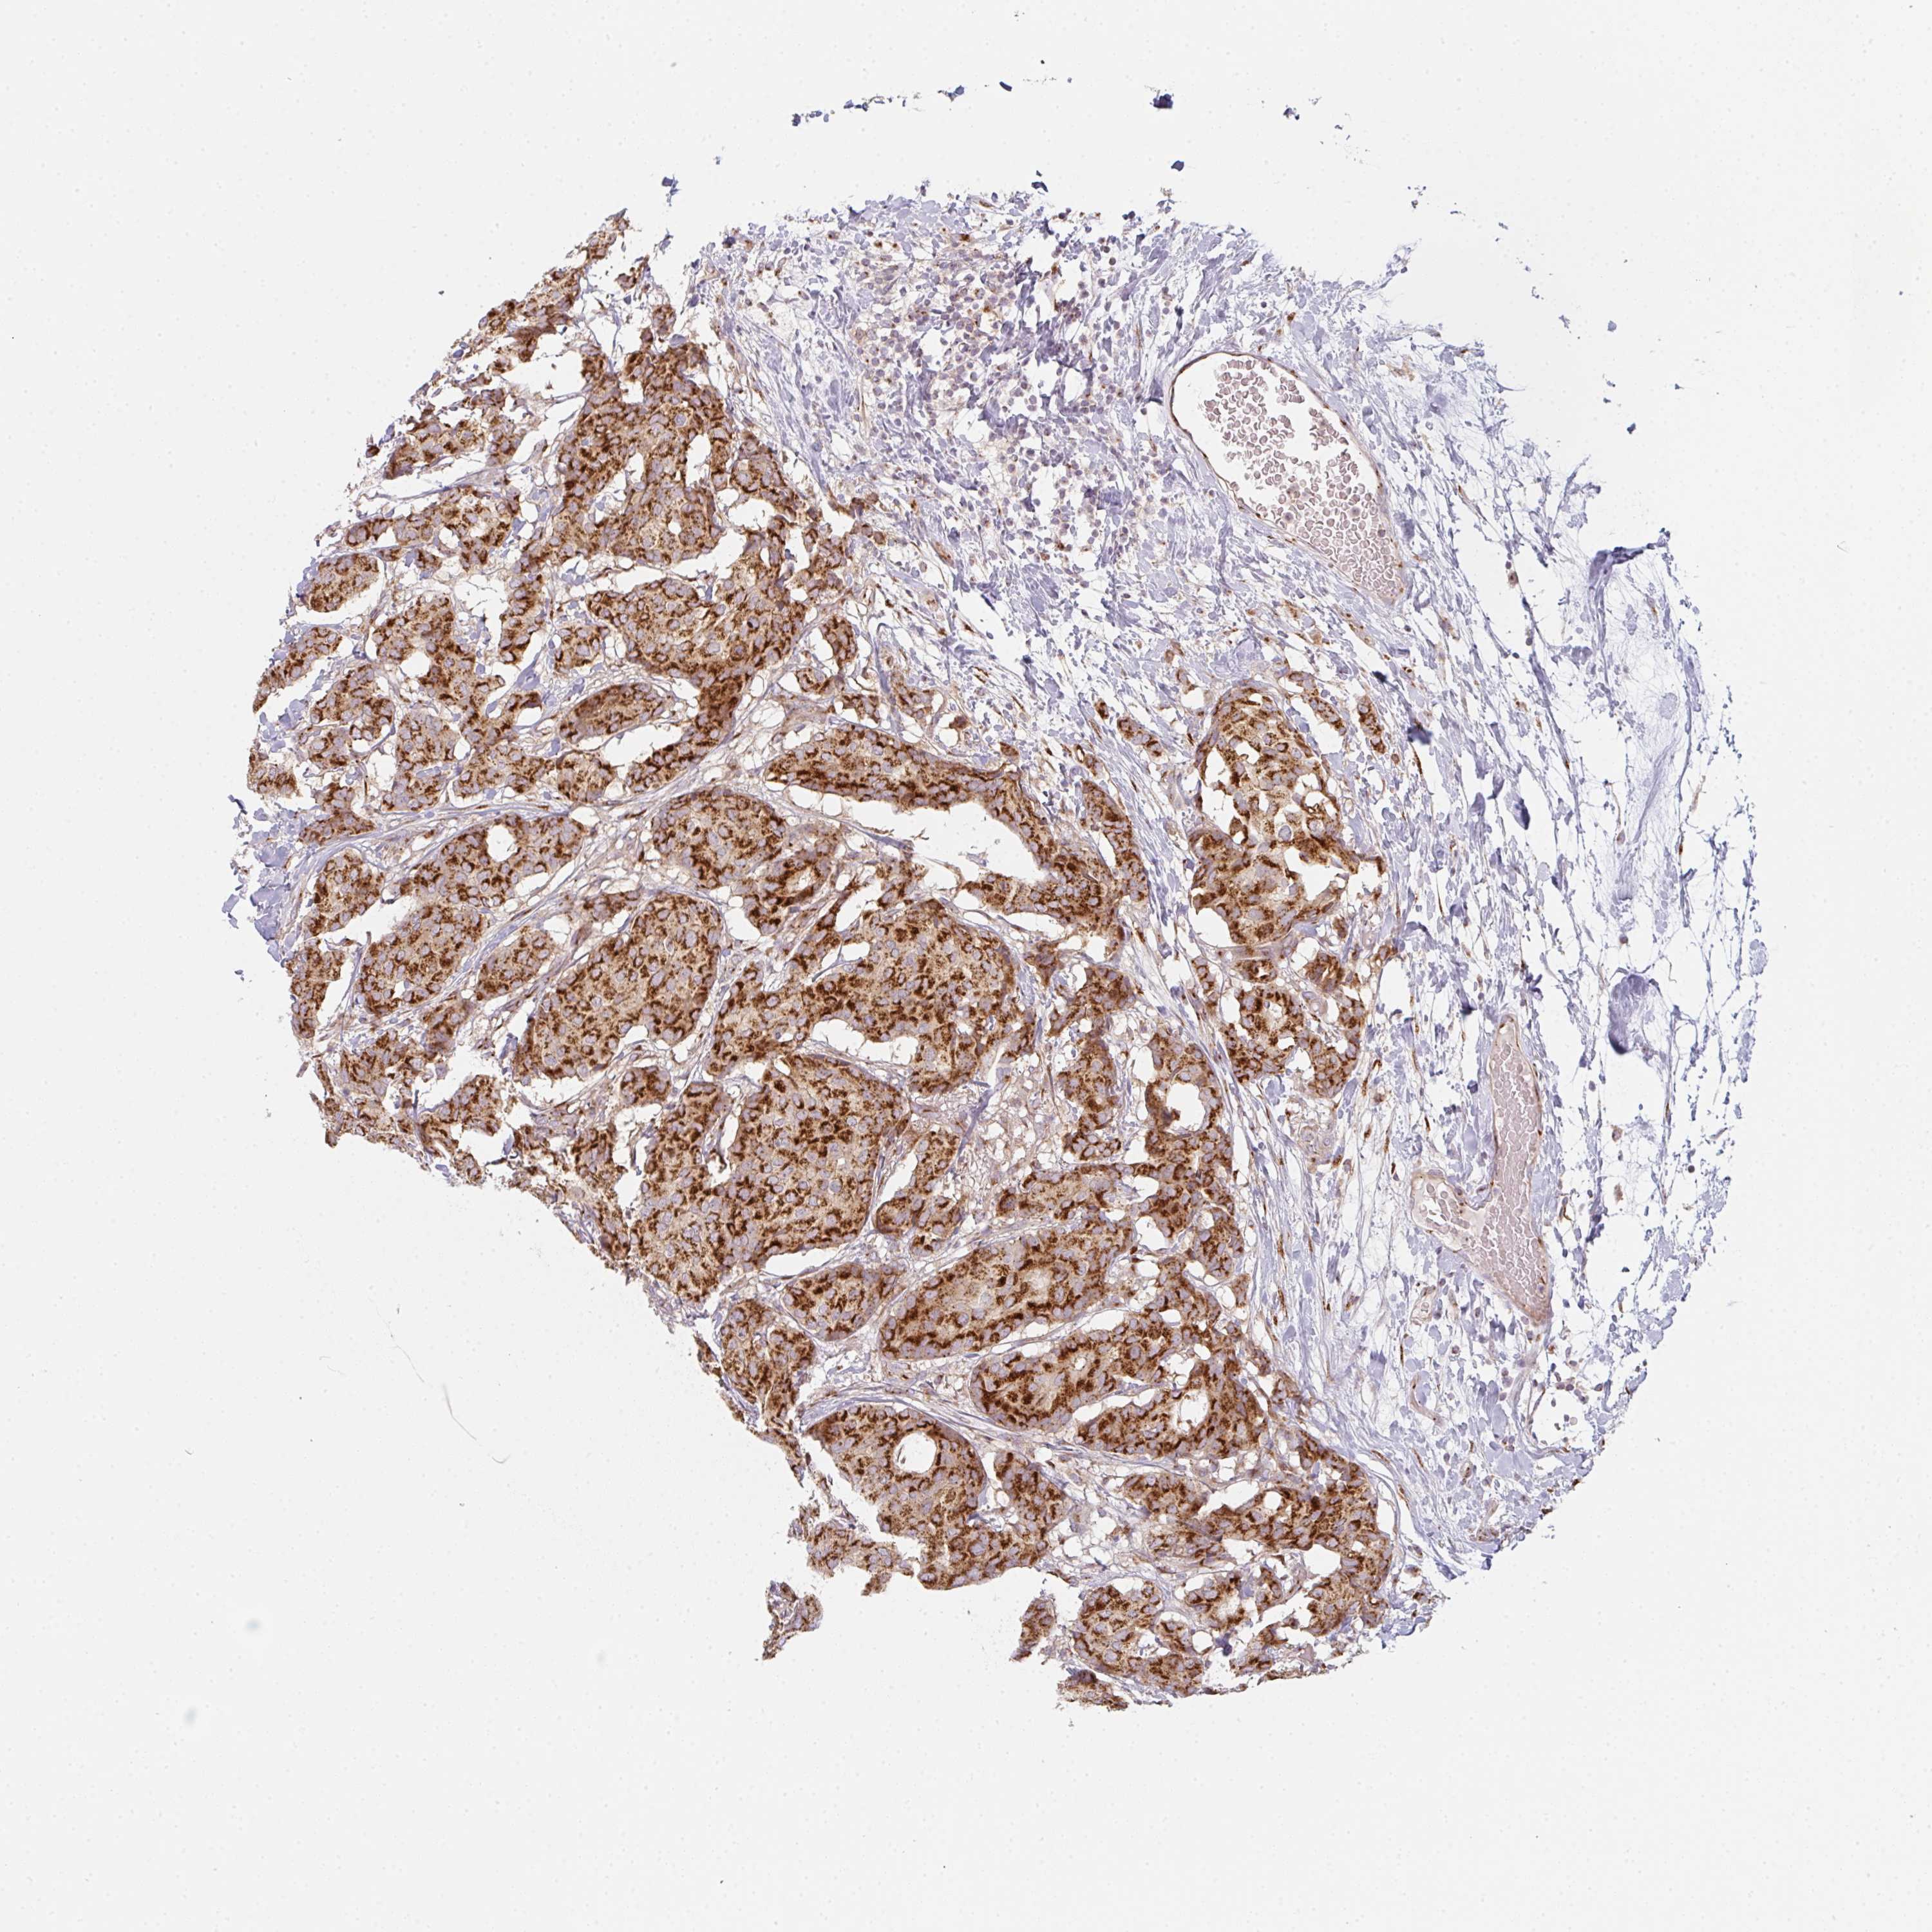

CANCER BREAST CANCER Show tissue menu

BRCA TCGA BRCA VALIDATION PROTEIN EXPRESSION